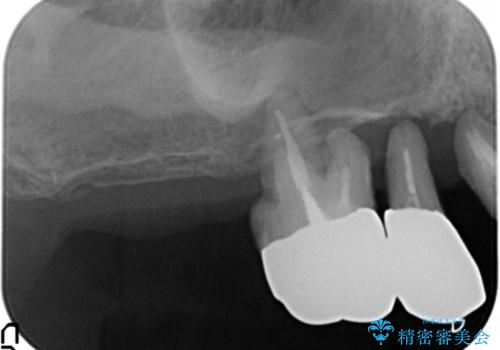

精査したところ、歯周病に罹患した歯を長年放置したことから骨吸収が進行し、上顎骨の厚みはとても薄くなっていました。

全顎的な歯周病治療を行ったのち、上顎洞底挙上術(上顎骨に骨を増やす手術)を併用したインプラント埋入を行いました。